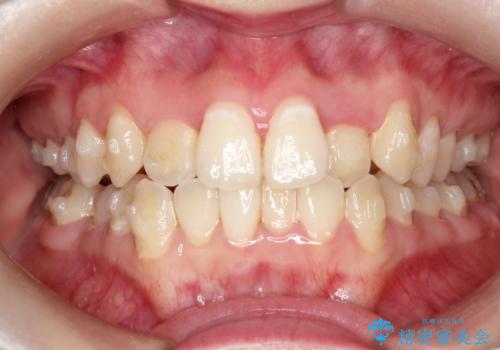

前歯が前後反対にかんでいる インビザラインによる矯正

- 前歯のがたつきを気にされて来院されました。

上顎の前から二番目の歯が内側に入り込んでおり、前後反対にかんでいる状態でした。

歯と歯の間にわずかに隙間を作り並べる計画としました。

しっかりとマウスピースを使用していただけたので、順調に治療を終えることができました。